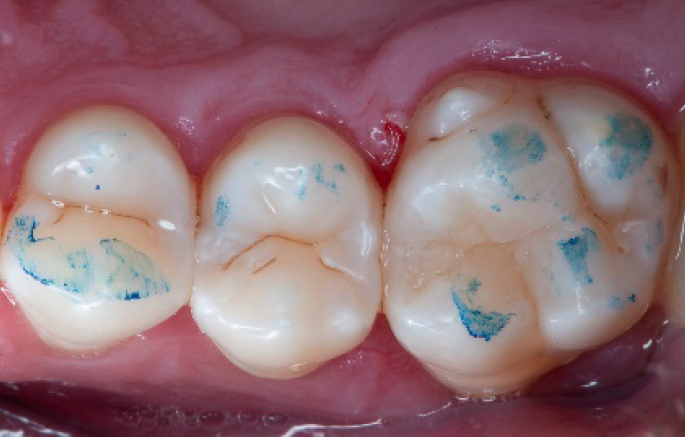

Step 12:

The situation after rubber dam removal.

Step 13:

Occlusal check

Step 14:

2 weeks control